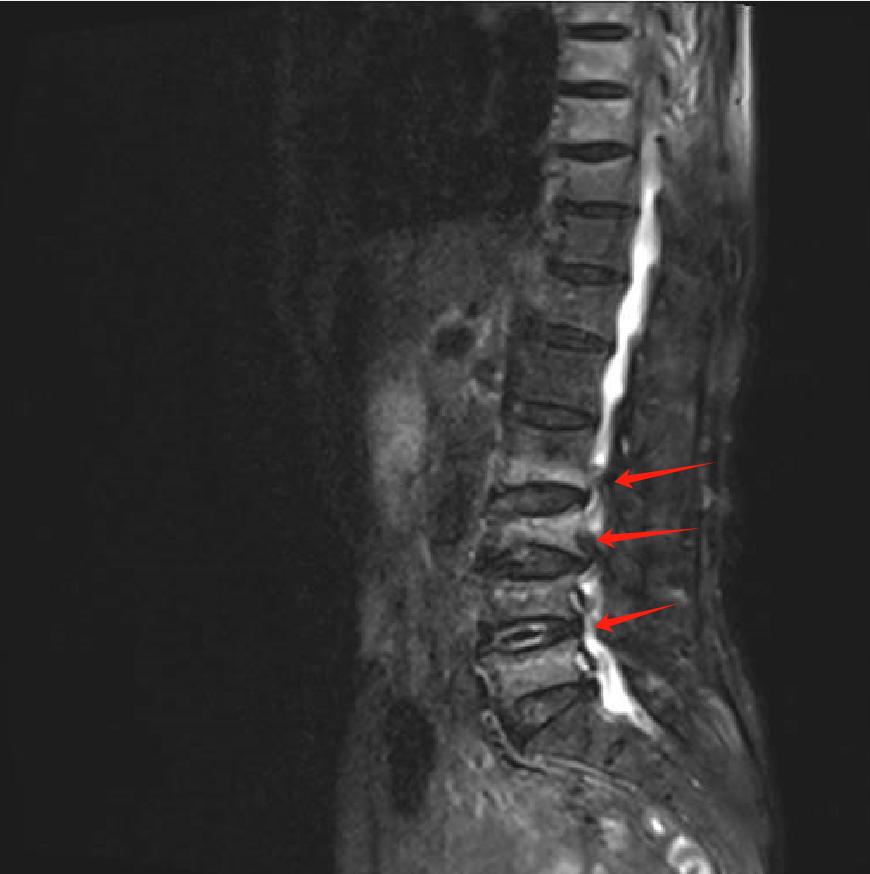

经磁共振检查发现,张婆婆因骨质疏松引发腰椎压缩性骨折,疼痛也随之而来。

腰痛背后的“隐形杀手”我国60岁以上人群中,骨质疏松症患病率超30%。轻微磕碰,甚至咳嗽用力,都可能导致椎体压缩骨折,引发持续腰痛、活动受限。张婆婆就是因腰椎L3、4、5节段骨折,疼到彻夜难眠,连翻身都成奢望。